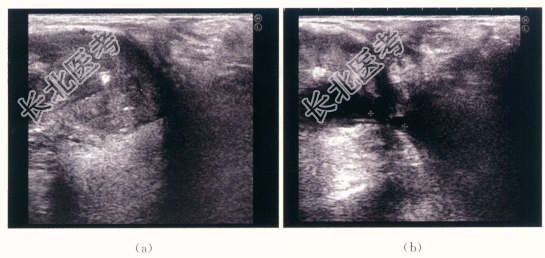

1.病史

患者,男性,32岁,因“后尿道重建术后2年,进行性排尿困难6个月”就诊。患者2年余前因外伤致骨盆骨折,膜部尿道断裂,于当地医院行急诊尿道会师术(具体不详),术后1个月拔出尿管后排尿尚可,在当地医院门诊间歇尿道扩张维持。近半年出现排尿困难,逐渐加重,1个月前出现尿滴沥,当地医院给予膀胱造瘘处理,患者为进一步诊治入院。

二、影像资料